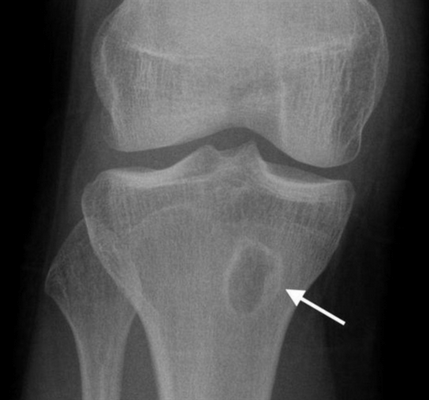

При появлении болей, отечности и тем более патологического перелома пациента направляют к травматологу-ортопеду. После опроса и осмотра больным традиционно показан рентген, что уже позволяет обнаружить патологические изменения в пораженной кости.

На рентгеновских снимках эозинофильная гранулема имеет вид литического очага округлой или овальной формы с четкими границами, расположенного преимущественно в костномозговой полости. При этом его размеры могут варьироваться в широких пределах. Как правило, признаки перифокального склероза отсутствуют. При поражении губчатой кости наблюдается так называемый пробойниковый дефект, а при локализации в позвоночнике может наблюдаться клиновидная деформация или формирование плоского позвонка. Таким образом, рентгенологическая картина при эозинофильной гранулеме не имеет специфических черт и во многом схожа с саркомой Юинга, остеогенной саркомой и другими злокачественными образованиями.

- Рентгенография костей. При рентгенологическом исследовании определяются единичные или множественные опухолевидные образования, участки деструкции, которые могут располагаться как в трубчатых, так и в плоских костях. При подозрении на эозинофильную гранулему обязательно проводят рентгенографию челюстей.